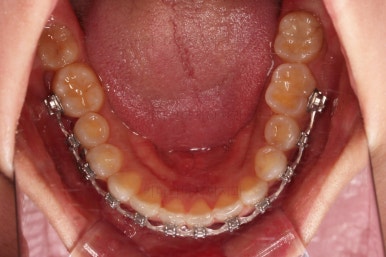

1. 초진

연산동교정치과 초진 시 입안의 모습입니다.

아랫니 어금니가 하나 없어서 주위 치아들이 해당 위치로 쓰러진 상태였습니다.